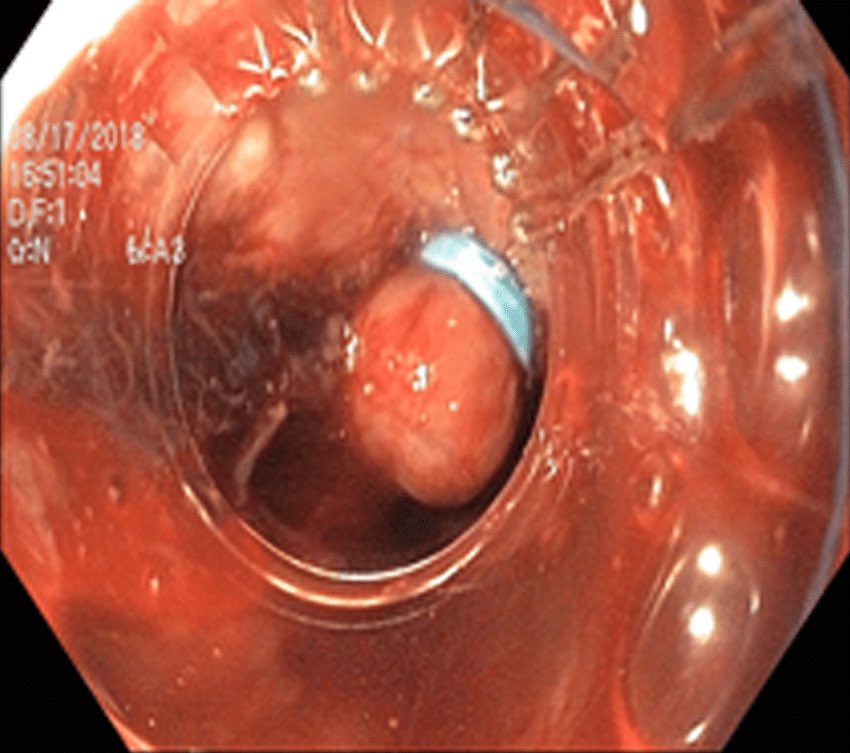

📍دوالي المريء عبارة عن أوردة غير طبيعية متضخمة

📍في الوضع الطبيعي اوردة المريء لا تظهر ولكن عند حدوث التليف يرتفع ضغط الدم في الوريد البابي وبالتالي يؤدي الى امتلاء أوردة المريء بالدم وبالتالي تظهر هذه الاوردة وتسمى بدوالي المريء ويتم اكتشافها بالمنظار او الاشعة المقطعية

🔆 أنواع دوالي المريء والمعدة

⛔️ تكون دوالي المريء عرضة للنزيف وعند حدوث النزيف تعتبر حالة طبية طارئة تستوجب التدخل الطبي العاجل

✅ لذلك يحرص الطبيب على اتخاذ كافة الاجراءات الوقائية لتجنب النزيف عند اكتشاف الدوالي عن طريق الفحص المبكر حيث ينصح كل مرضى تليف الكبد بعمل منظار الجهاز الهضمي العلوي عند التشخيص

✳️ وبعدها يتم عمل منظار علوي للجهاز الهضمي بغرض التشخيص والعلاج

📍ويتم علاج دوالي المريء عن طريق ربط الدوالي

📍ويتم علاج دوالي المعدة عن طريق الحقن او باستخدام منظار الاشعة الصوتية

📍وبعد علاج حالة النزيف يتم اكمال مواعيد المناظير لاكمال ربط الدوالي المتبقية على عدة جلسات